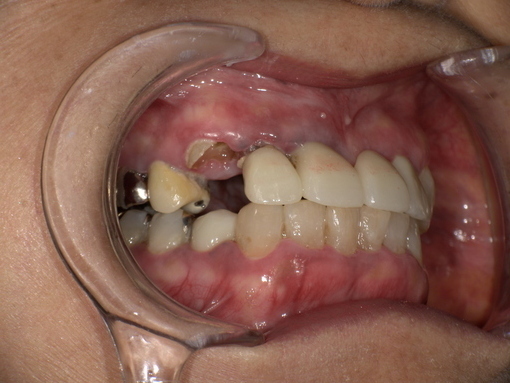

歯の詰め物(金属・銀歯)や薬剤の影響

古い銀歯や金属製クラウンから金属イオンが溶出し、口腔粘膜との接触でアレルギー反応が生じる場合があります。クロム・ニッケル・金・水銀などが原因物質となることがあり、金属アレルギーのある人は特に注意が必要です。